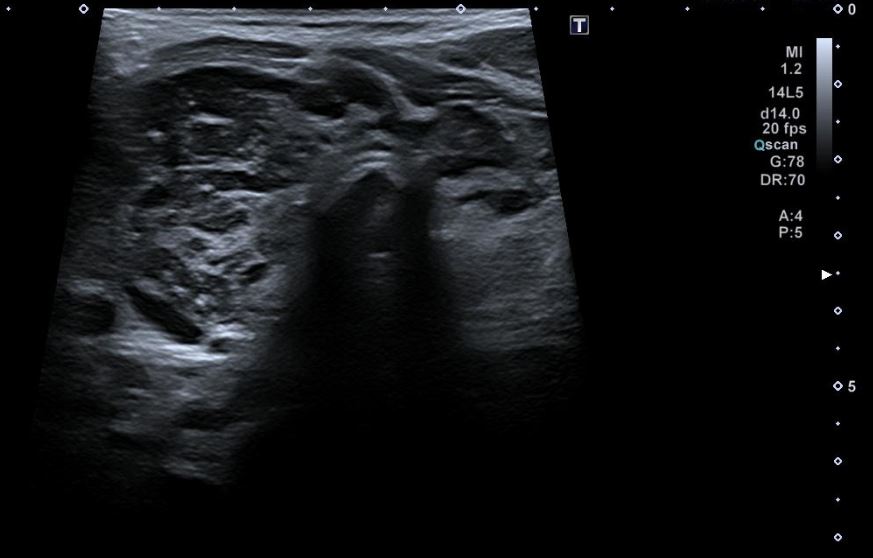

Una vez realizada la anamnesis y la exploración física, se decide realizar una ecografía clínica en la consulta, donde se objetiva un aumento difuso de tamaño del lóbulo tiroideo derecho (33,9 x 38,7 mm), levemente hipoecogénico, con áreas anecoicas en su interior y adenopatías asociadas. Se aplica Doppler color resultando positivo.